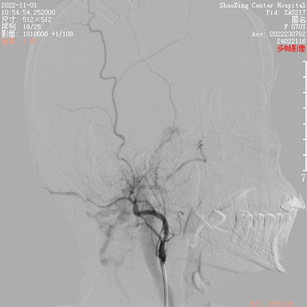

患者入院2月前无明显诱因下出现左侧耳鸣,呈吹风样,持续性,节律与脉搏一致,无明显加重缓解因素,声音与头位或体位无关,无头痛头晕,无恶心呕吐,当时就诊当地医院对症处理,无好转。入院1天前就诊于当地医院查MRA(图1)及脑血管造影(图2)提示“左侧颈外动脉造影见咽升动脉供血通过岩上窦、海绵间窦向双侧颈内动脉引流的动静脉瘘。左侧椎动脉造影显示左侧椎动脉开口无狭窄,椎动脉硬膜支供血向同侧椎旁静脉引流的瘘形成”,现为进一步治疗来院。

根据病史及当地医院辅助检查,诊断后颅窝硬脑膜动静脉瘘明确。分析当地医院MRA及血管造影结果,大致可判断该患者瘘口位于左侧舌下神经管或髁前汇区。详细读片可见左侧颈外动脉造影及椎动脉造影所示引流模式相同。入院后完善脑血管造影检查,并应用双容积影像后处理技术进行三维重建(图3)。便于进一步分析血管构筑,制定手术策略。